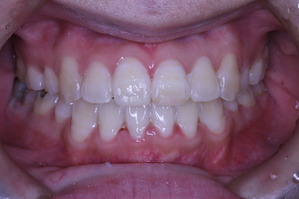

治療終了時です。

初診の状態と比較していただければ、仕上がりの状態がより理解できると思います。